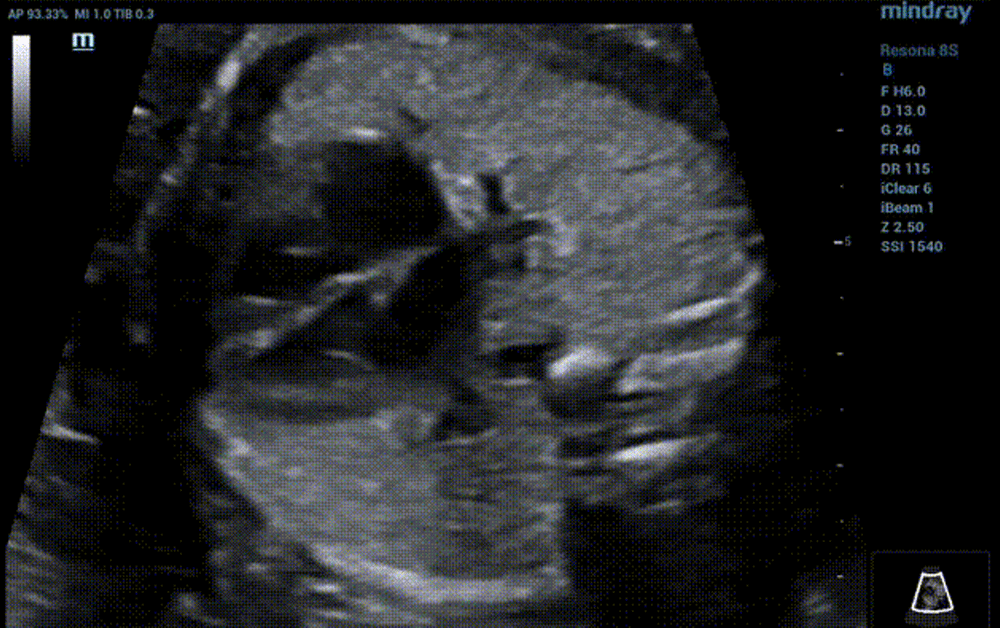

Four-chamber view

• The heart is located in the left chest and apex pointing to the left, CTR 0.27.

•  Concordant atrioventricular connection. Normal ratio of left and right atrium diameter, a little hyperechoic in the LV. Normal shape and function of atrioventricular valve.

•  The consistent connection between ventricle and a great artery .Normal original and size of aorta and pulmonary artery, blood flow unobstructed. Normal Semilunar valve shape and function.

•  Normal course and diameter of ductus arteriosus and aortic arch, and unobstructed blood flow.

•  The superior and inferior vena cava return to the right atrium, and one pulmonary vein return to the left atrium.

•  Normal fetal heart rhythm, HR 142 bpm.

By now, everything is normal. The preliminary diagnosis suggested no significant abnormality in fetal heart structure at present. However, when the probe is slightly tilted from the standard four chamber view to the fetal foot side, the problem occurs: